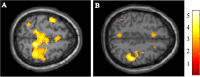

Results: Patients with PD performed significantly worse in terms of the correct answer rates of all n-back tests compared with HC. fMRI analyses performed during the 2-back test revealed reduced activation in the bilateral dorsolateral prefrontal cortex, middle frontal gyrus (MFG), and parietal lobule in the PD group compared with the HC group. In contrast, the fMRI result during the 0-back test showed only a marginal difference in the frontal lobe. On comparisons of task performance between the PD-MCI and PD-CN groups, we found that the correct answer rate in the 2-back test was lower in the PD-MCI group than in the PD-CN group. However, scores of the 0-back and 1-back tests were not significantly different between the two groups. The fMRI findings revealed that activations within the middle frontal gyrus (MFG) and inferior parietal lobule (IPL) during the 2-back test were reduced in the patients with PD-MCI when compared to those with PD-CN.

Conclusions: This study reports reduced activation of the MFG and IPL in patients with PD-MCI. These regions may be associated with the pathophysiology of working memory impairment in patients with PD, which involves fronto-striatal network dysfunction.